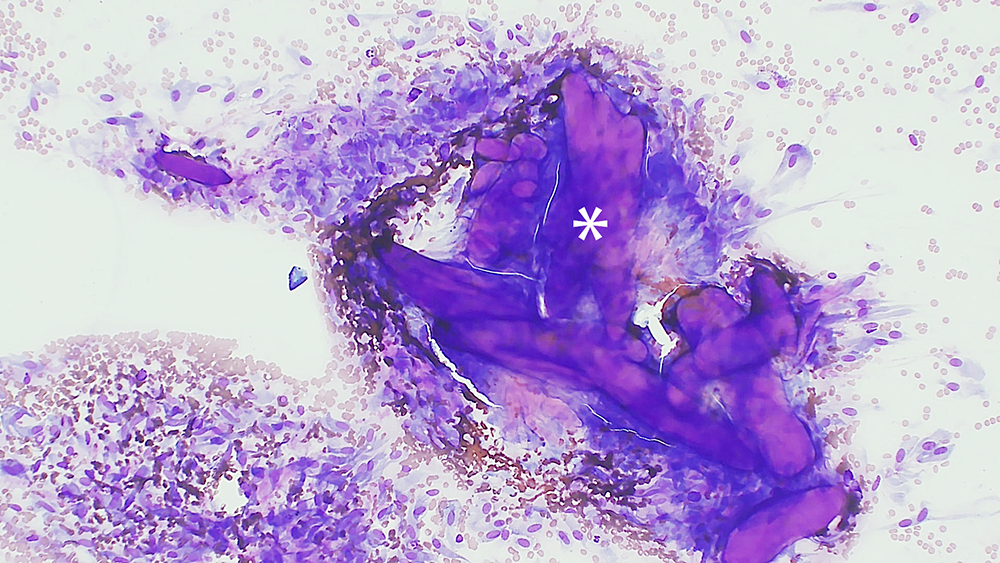

One pre-stained (Diff-Quik) slide was examined and showed a highly cellular population of spindle to occasionally stellate cells (Figures 1 and 2). Individual and aggregates of cells were often associated with extracellular eosinophilic matrix ranging from fibrillar to glassy in appearance, consistent with hyalinized collagen. The cells showed moderate to abundant amounts of mid-blue cytoplasm with tapered ends. The cells had ovoid to rarely round nuclei with finely stippled chromatin and one to three small nucleoli. There was mild to moderate anisocytosis and anisokaryosis. No mitotic figures were seen. There were rare well granulated mast cells scattered throughout.

Figure 1: Fine needle aspirate of a subcutaneous keloidal fibroma from a 3-year-old male castrated dog. Hyalinized collagen surrounded by neoplastic spindle to stellate cells. Diff-Quik, 100x magnification.

Figure 2: Fine needle aspirate of a subcutaneous keloidal fibroma from a 3-year-old male castrated dog. Higher magnification view of the hyalinized collagen surrounded by neoplastic spindle to stellate cells. Diff-Quik, 200x magnification.